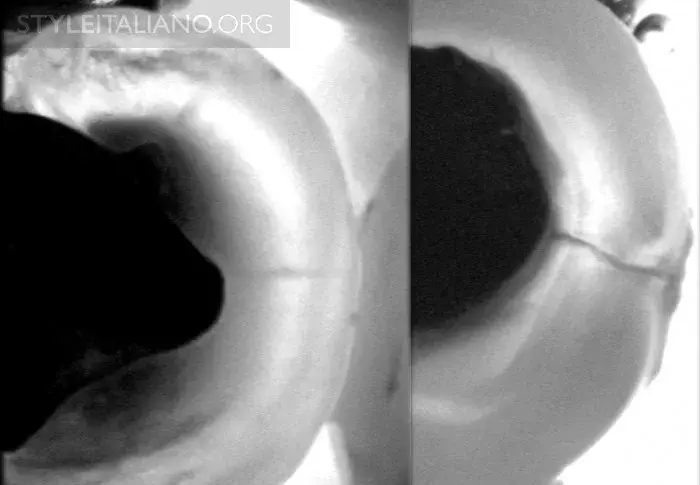

Рис. 8 – Фиссура - одна из анатомически сложнейших областей зуба. Мы можем получить представление о происходящих в ней процессах - фиссурном кариесе.

Скрытый кариес

Рис. 9 – Предварительная рентгенограмма. Скрытый кариес: кариес дентина на окклюзионной поверхности. Деминерализация достаточно большая, чтобы обнаружить ее с помощью просвечивания.

Рис. 10 — Раскрытие полости.